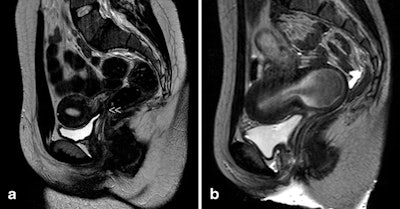

![Urogenital sinus anomalies. MR images [(1) T1- and (2) T2-weighted fat-suppressed images in the sagittal plane] show a retrovesical blind vagina with apparent inferior half atresia and undetected fistula tract to the bladder (](https://img.auntminnieeurope.com/files/base/smg/all/image/2016/08/ame.2016_08_26_16_04_51_413_female_genital_malformationspic3.png?auto=format%2Ccompress&fit=max&q=70&w=400)